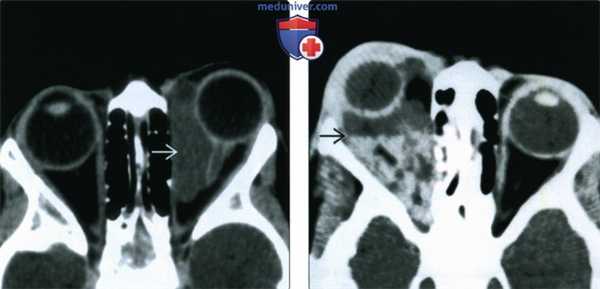

(Слева) При аксиальной МРТ Т1 ВИ FS с КУ определяется утолщение хориоидеи заднего отрезка левого глазного яблока и распространение опухоли через верхнюю глазничную щель в кавернозный синус. Из-за большого объема экстраокулярного поражения и обширной опухолевой инфильтрации этот случай не типичен.

(Справа) При МРТ Т2 ВИ в аксиальной проекции регистрируется характерный низкий Т2 сигнал как внутриглазного, так и экстраокуляр-ного компонентов инфильтративного новообразования, что подтверждает диагноз меланомы глаза.